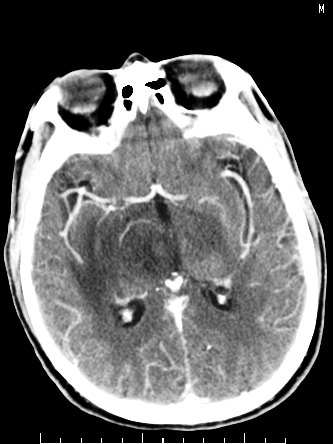

m/50,头昏头痛1月,近3天感觉左半肢体活动不利,自述半年前呈患肺tb,腰穿脑脊液未见特殊改变。现做头颅ct请大家会诊。

考虑颅内感染性病变:结核可能性大。

结核性脑膜炎,结核瘤,梗塞灶三症并存,提示颅内结核感染可能性大。

感染性病变;脑干脓肿(脓肿壁形成期),基底节及内囊(脑炎期)。顺便问一句,该病人是不是抵抗力很差,有没有糖尿病。

右侧基底节区缺血性脑梗塞.脑干区考虑结核.